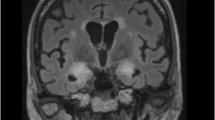

Imaging

Cerebral imaging has already proved its significance in oncology for the detection of tumor progression or infection-related complications. Recent advances in quantifying software have facilitated highly precise assessment and intra- or inter-individual comparison of various changes, including ischemic or inflammatory alterations [47,48,49]. The application of quantitative cerebral imaging in neurology can be beneficial in the oncological sector for the precise quantification of brain volume reduction and leukoencephalopathy. This approach can be useful for individual disease monitoring and standardized examination of medication side effects in a research setting, such as comparing leukoencephalopathy development under different chemotherapy regimens or radiation schemes.

Based on the risk profile, additional diagnostic tests such as EEG, electrophysiological examinations, or cerebral/spinal imaging may be required to classify pathological findings during or after the treatment cycle or to take specific preventive measures before the initiation of therapy, like an adjustment of dosage of anti-seizure medication. In case of acute neurological complications, close interdisciplinary cooperation should be guaranteed, enabling to conduct targeted diagnostics. At the end of the hospital stay, a neurological final examination with recommendations for further outpatient treatment, e.g., regarding physiotherapy or medication adjustment, can contribute to advance recovery of oncological patients, resulting in an improvement of their quality of lives. Figure 3, which can be find at the end of this section, illustrates an exemplary patient pathway for neurological monitoring during CAR T-cell therapy, which serves both patient care and scientific inquiries.

Example 1: A patient with advanced lymphoma presents for CAR T-cell therapy. In addition to structural epilepsy after stroke, the patient has developed a length-dependent peripheral neuropathy due to several chemotherapy cycles as well as cognitive and amnestic deficits that impair daily life. In the inpatient setting, the patient undergoes a general neurological baseline examination, a neuropsychological testing, a cerebral MRI, NfL determination, and an EEG, on the basis of which the seizure-suppressing medication is administered prior to CAR T-cell therapy. Seven days after CAR T-cell therapy, the patient develops severe ICANS with recurrent epileptic seizures. MRI shows a mild ubiquitous barrier disturbance without any other changes from the initial findings. In addition, there is a significant increase in NfL. After ruling out all relevant neurological differential diagnoses, high-dose methylprednisolone therapy is initiated immediately. The seizures cease with a readjustment of the seizure-suppressing medication. Regular neurological follow-up examinations show rapid improvement of symptoms. The mild sensorimotor hemiparesis can be classified as pre-existing based on findings of baseline examination. Due to ongoing fine motor impairment and tremor symptoms, a neurological rehabilitation measure is initiated. However, the patient is readmitted 1 week after discharge with suspected biphasic ICANS. A comparison of the neurological findings cannot objectively confirm any neurological deterioration, and the neurofilament has returned to its baseline level prior to CAR T-cell therapy. After ruling out infectious or metabolic complications, the patient is diagnosed with suspected chronic fatigue syndrome, and rehabilitation measure can be continued. Three months later, the patient presents for clinical follow-up in the neuro-oncological outpatient clinic. A described deterioration in memory function can be objectively verified by neuropsychological testing. However, the testing also suggests possible causal depression. Under antidepressant medication, the patient’s memory function stabilizes over time which can be confirmed by the further neuropsychological examinations.